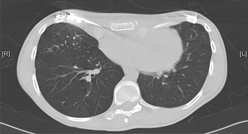

Alle Operationsverfahren bei gut- und bösartigen Tumoren der Lunge werden angeboten,...

Videoassistierte Entfernung einzelner Lungenblasen (Bullae) bei Pneumothorax dienen der Prophylaxe vor einem Rezidiv, d.h. Wiederauftreten des Lungenkollaps...

Im Februar 2011 wurde die Entfernung eines ganzen Lungenlappens bei Lungenkrebs über eine „Schlüssellochtechnik“ mit dem daVinci...